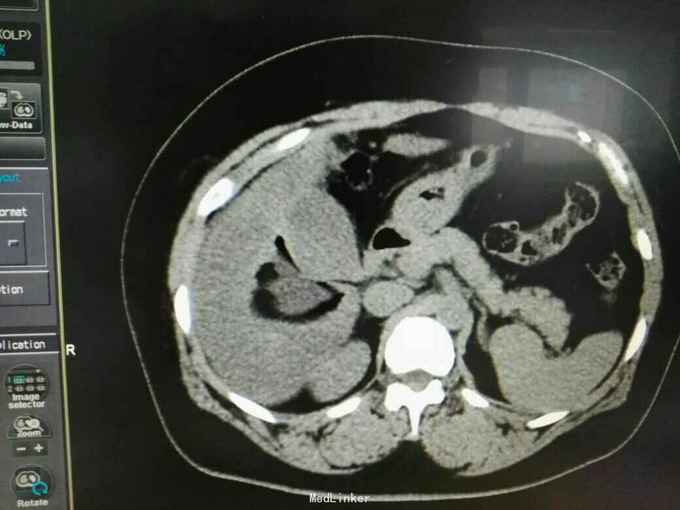

巨大肝囊肿

发现肝脏占位10年

肋弓下可触及囊性占位

肝囊肿

今日在局麻下行囊肿穿刺抽吸+无水酒精注射术 术中共抽取淡黄色液250ml